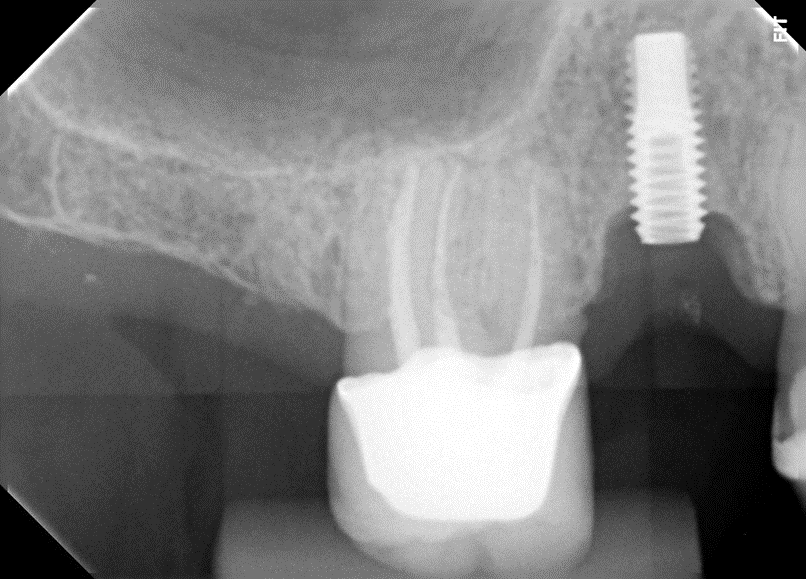

No presente caso, o paciente procurou nossa clínica acreditando que a coroa sobre implante do 15 estava apenas frouxa, e que seria possível resolver apertando o parafuso. Ao exame clínico, apresentava uma coroa cimentada sobre componente UCLA fundida e parafusada diretamente sobre o hexágono do implante (um HE de 3.5 mm de diâmetro e plataforma da mesma medida). Após o corte da coroa para acessar o parafuso, na remoção do conjunto, a plataforma do implante veio anexada à coroa, denotando a fratura do implante, que foi comprovada com radiografia periapical (Figuras 1 e 2). Decidimos por fazer uma prótese adesiva provisória (Figuras 3 e 4) e planejar a remoção do implante com colocação imediata de novo implante, após observado na tomografia cone beam que haveria osso suficiente para isso (Figura 5). O implante foi removido (Figuras 6 e 7) com o uso de broca trefina e fórceps, e um implante Implacil De Bortoli CM Due Cone foi instalado no mesmo momento (Figura 8), com regeneração óssea guiada (ROG) na parede vestibular (Figura 9), que havia ficado muito fina (enxerto ósseo particulado + membrana de colágeno). Apesar de termos obtido bom travamento do implante (45 Ncm), optamos por deixá-lo sem carga pelo período de cinco meses, para respeitar o tempo da ROG (Figuras 10 e 11).